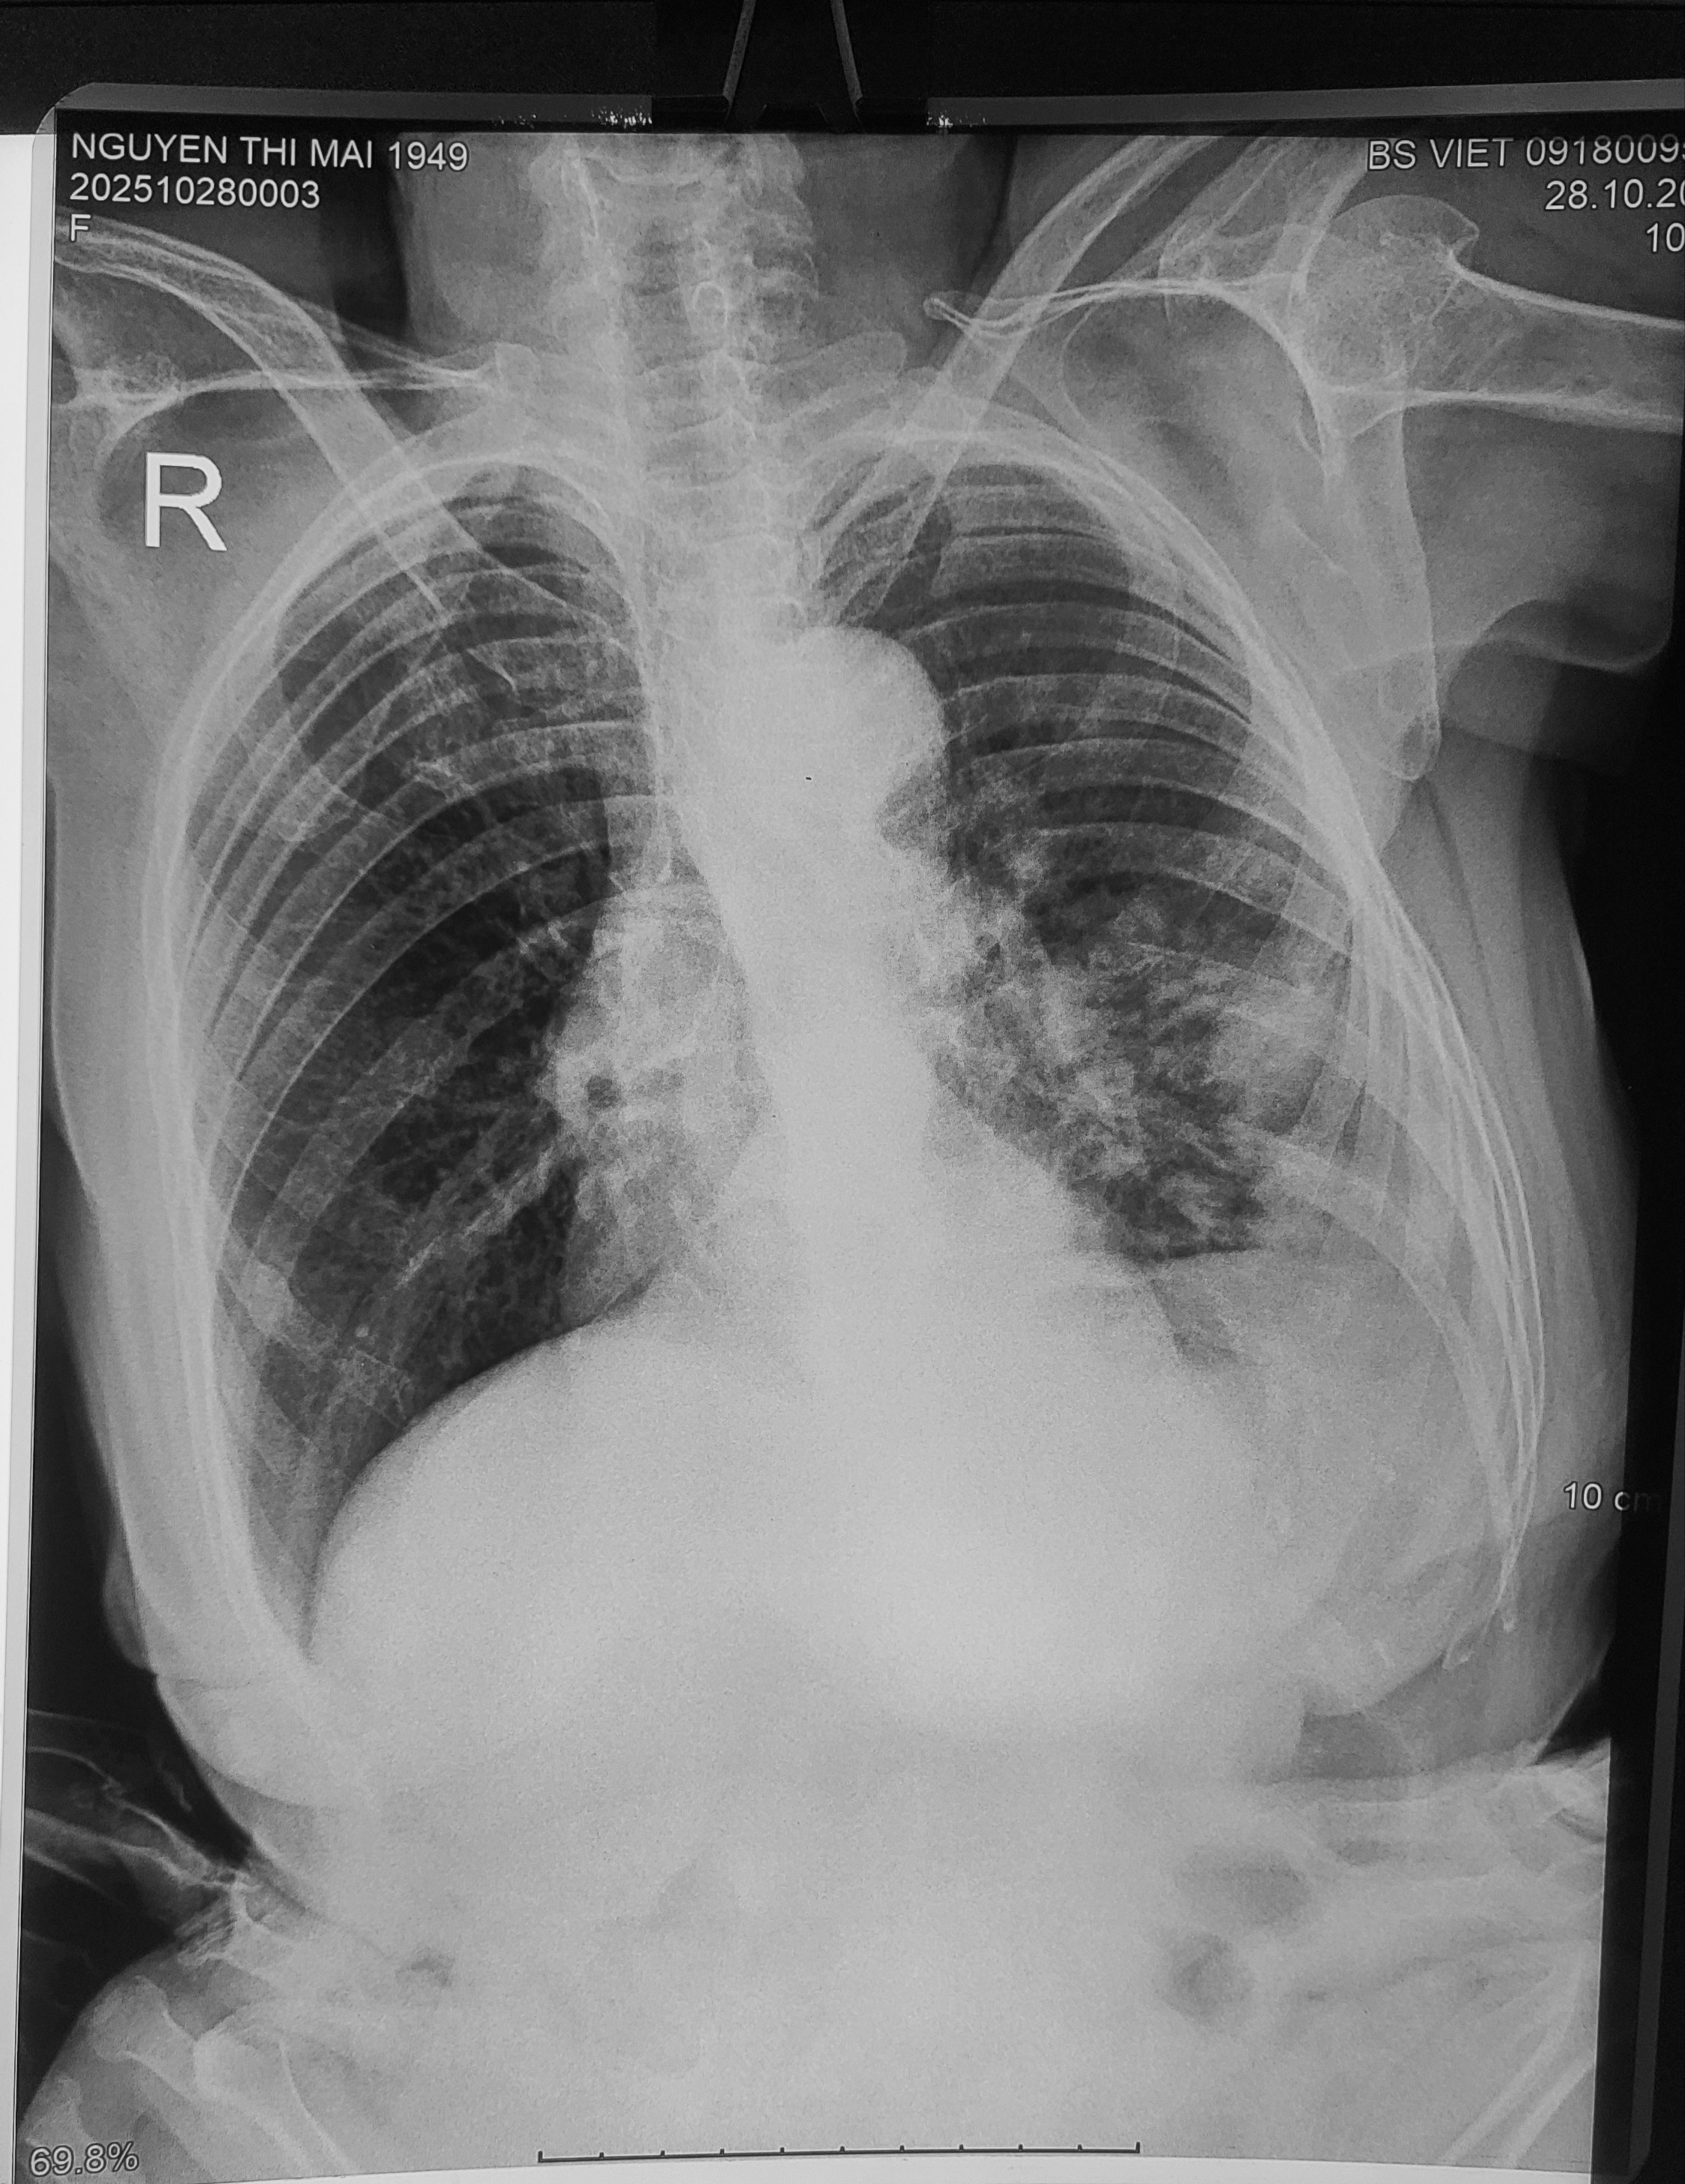

#xq Bn nữ 68t đau lưng, lan xuống mông, đùi, cẳng chân

.

Nhận định cá nhân: Trượt đốt sống L4 ra trước (độ 1). Hẹp khe đĩa đệm L4-L5, L5-S1. Gai xương L3-L4